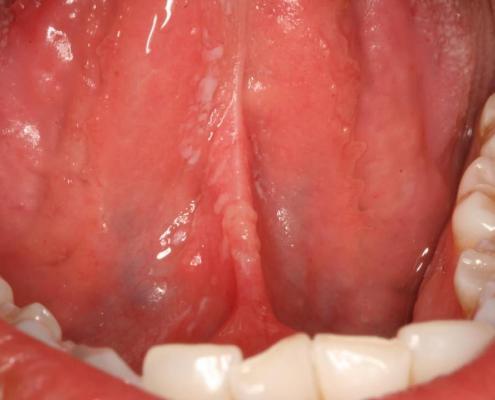

Diagnóstico Precoce do Câncer Bucal: Um Tema Repleto de Desafios

O carcinoma de células escamosas é a principal neoplasia maligna…

Melanócitos na mucosa oral? Por que eles estão ali?

Os melanócitos são células responsáveis pela produção de…